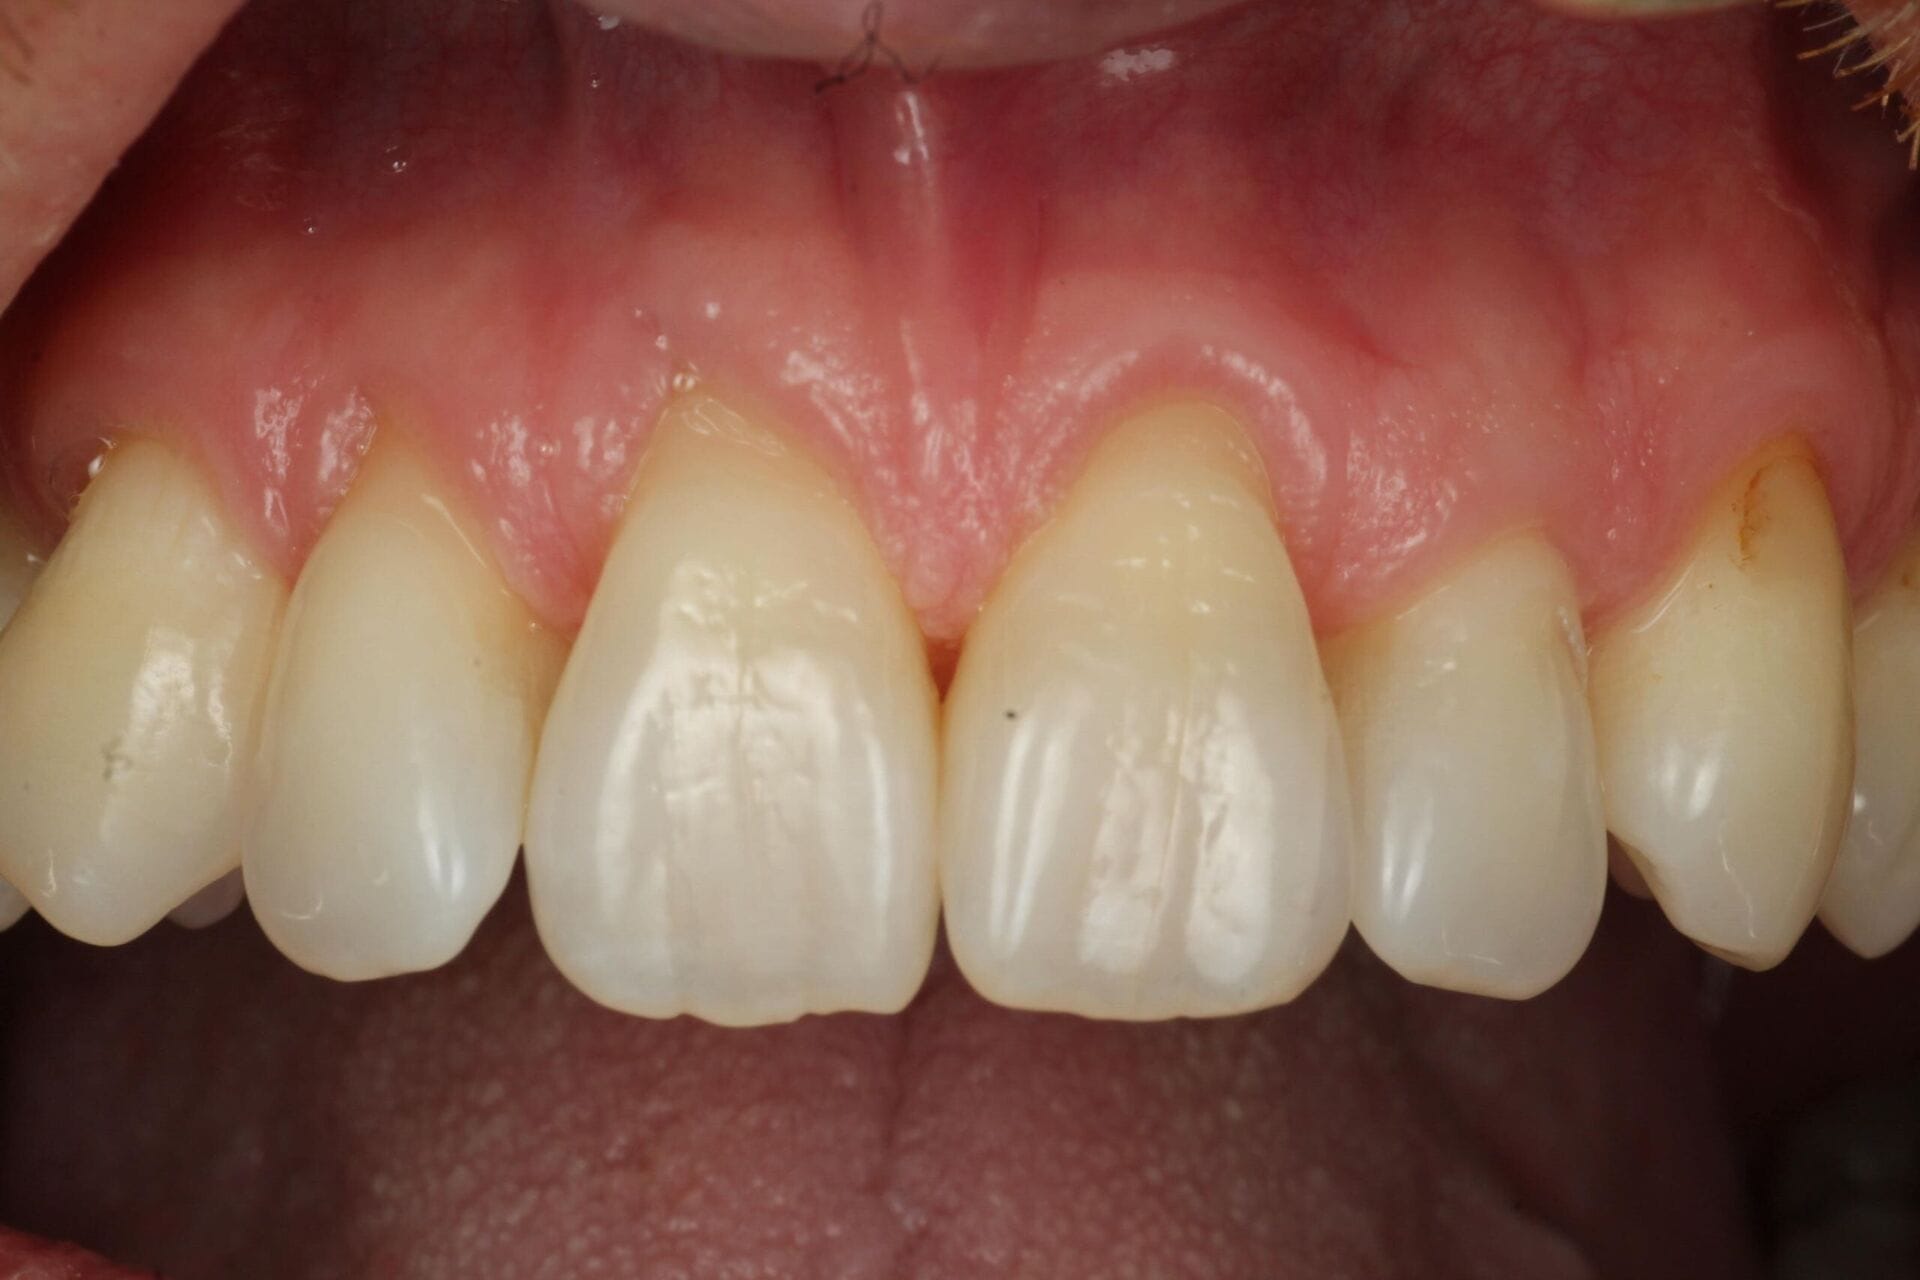

Here at 76 Harley Street, we are proud to offer gum disease treatment and prevention therapy where we can help treat, manage and prevent patients suffering from gum disease. Dr Hiten Halai and Dr Tay Shiehfung, our specialist periodontists, provide gold standard care in common cases of bleeding gums, gum recession, loose teeth, bad breath and bone loss.

Healthy teeth need healthy gums and if you are concerned you are suffering with gum disease we highly recommend seeking expert advice. Dr Hiten Halai and Dr Tay Shiehfung provide private specialist treatment and care for all types of gum treatment.

Gum disease, or periodontal disease, is a common but serious condition that affects the soft tissues and bone supporting your teeth. It typically starts with gingivitis; swollen, red, or bleeding gums caused by the buildup of plaque and tartar. If untreated, it can progress into periodontitis, leading to gum recession, bone loss, and even tooth loss.